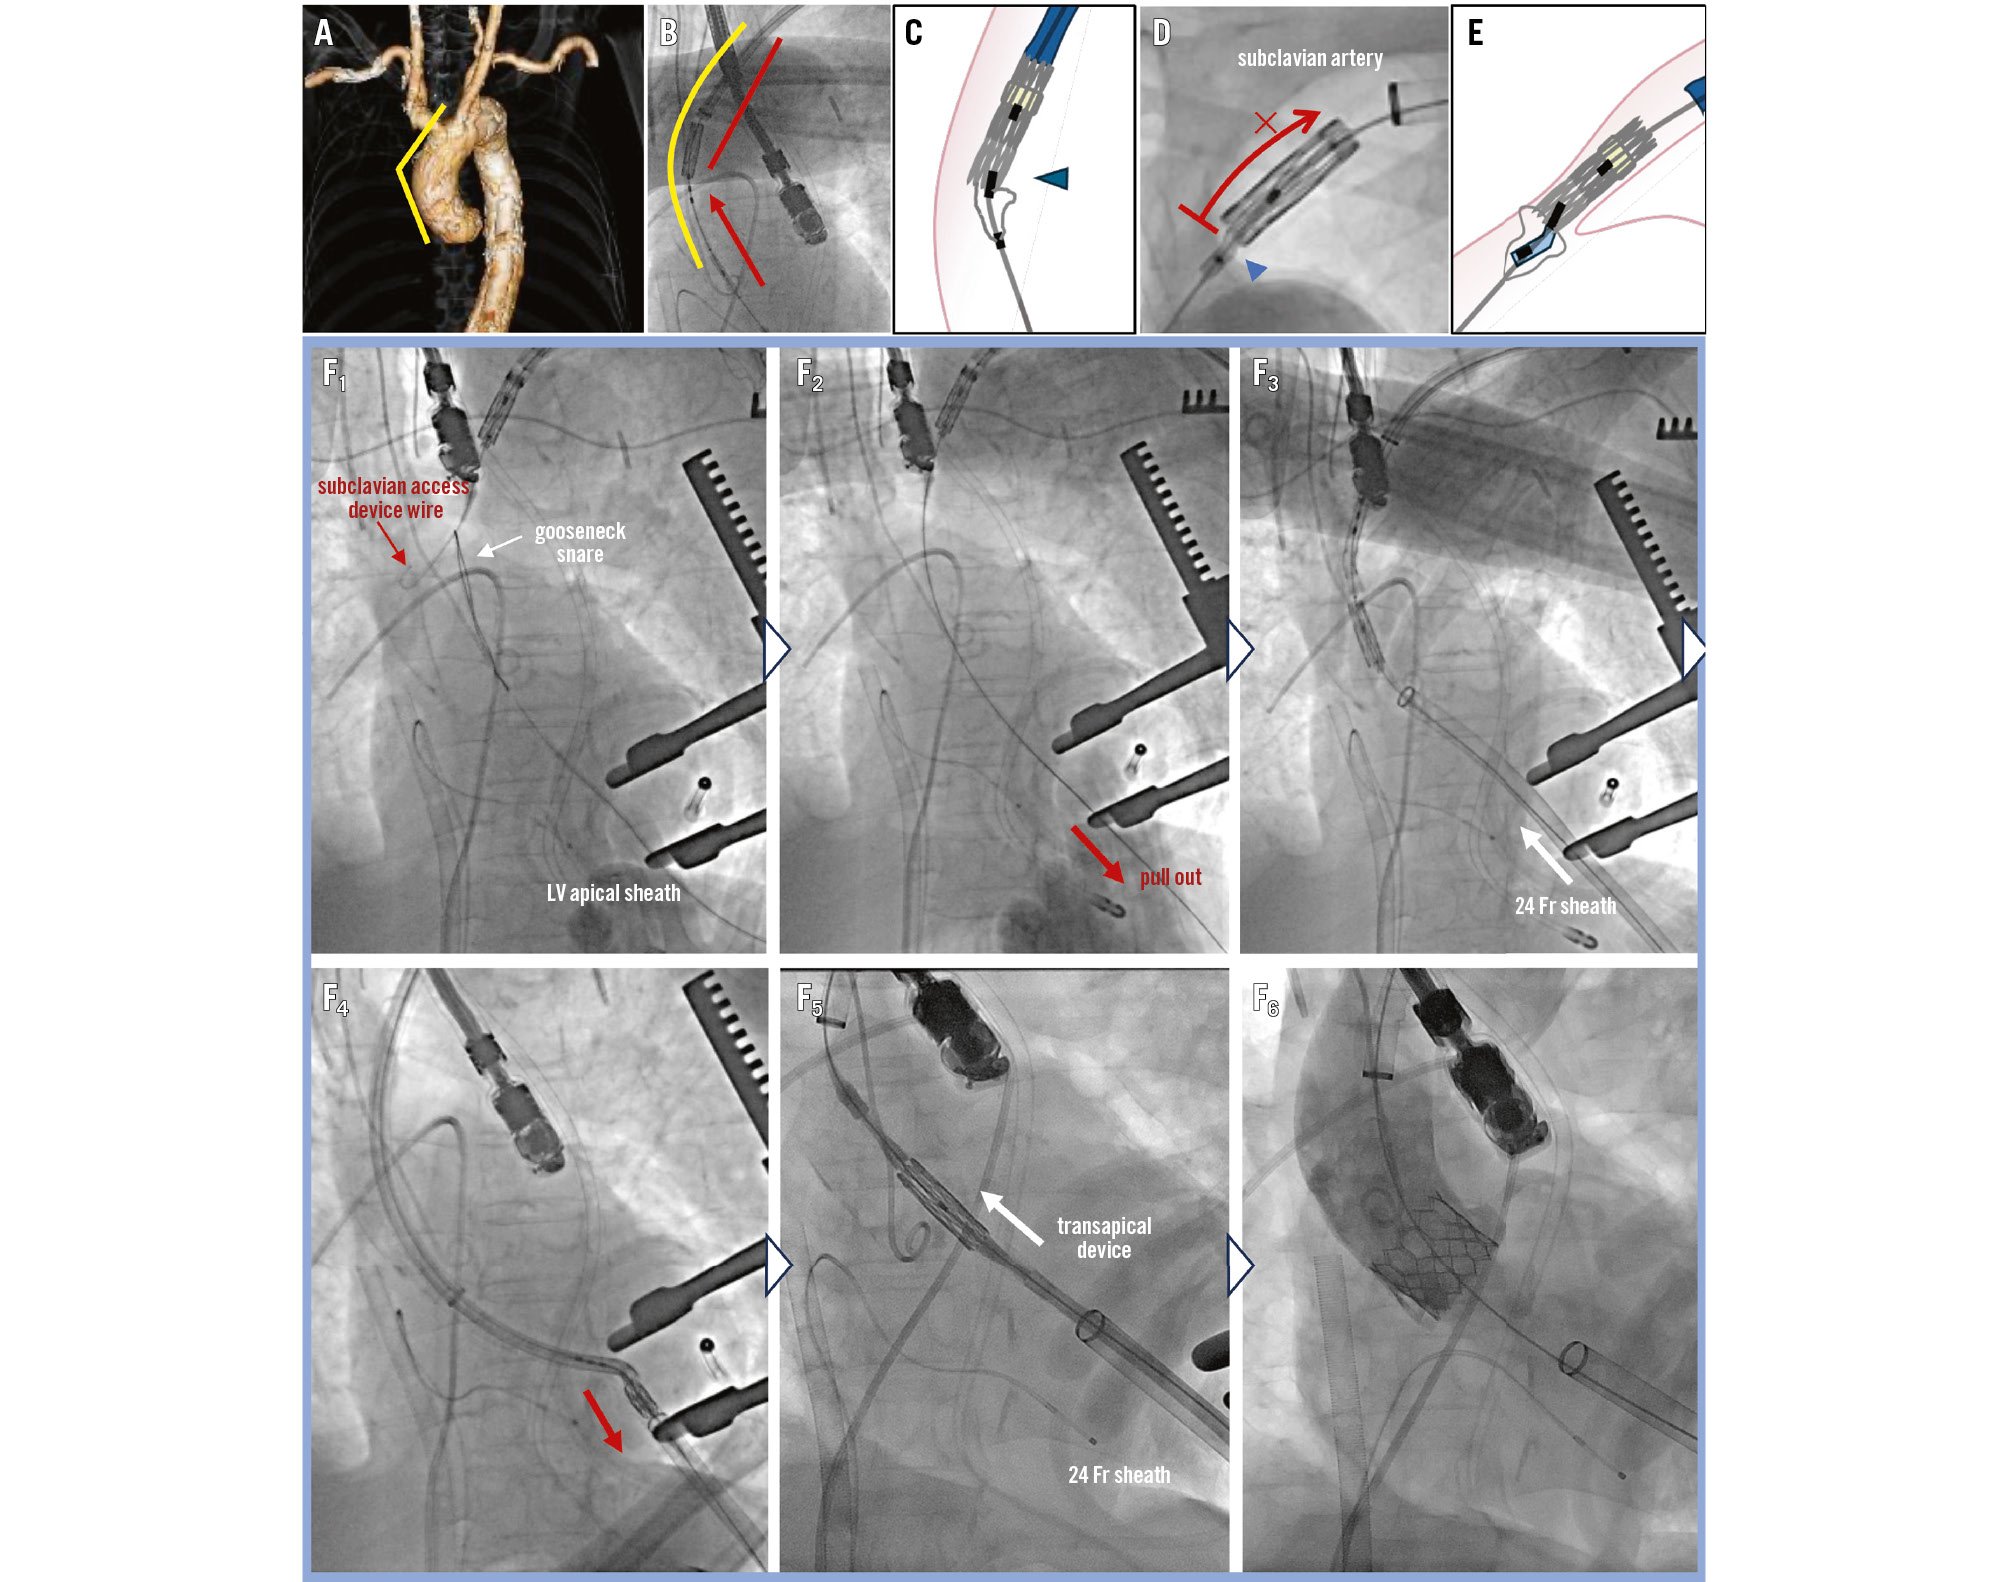

Given the patient’s comorbidities and haemodynamic instability, the Heart Team opted for urgent transcatheter aortic valve implantation (TAVI) using a 26 mm SAPIEN 3 valve (Edwards Lifesciences). Left subclavian access was chosen because both femoral arteries were occupied by ECMO and IABP devices. With a vessel diameter of >6 mm, aortic arch angle of 120°, and ascending aorta length of 74 mm, the left subclavian route was deemed feasible (Figure 1A). An 18 Fr sheath was inserted into the aortic arch over a SAFARI XS wire (Boston Scientific). The prosthetic valve with its delivery system was advanced into the ascending aorta, and prosthesis-balloon alignment was attempted, notably near the aortic arch (Figure 1B). However, strong resistance disrupted alignment at the balloon’s midportion, preventing withdrawal to the warning marker. The balloon could only mount two-thirds of the valve, and fracture of the unretractable distal balloon shaft was confirmed (Figure 1C, Moving image 1). Blood return from the inflation device indicated balloon rupture. Removal via the subclavian artery was impossible because of the deformed balloon obstructing passage (Figure 1D, Figure 1E).

Ultimately, the stuck prosthesis and delivery system were retrieved via the LV apex. After LV apex puncture via a standard transapical approach, the stiff wire of the SAPIEN delivery system was folded using a 10 mm gooseneck snare from the LV apical sheath (Figure 1F1) and pulled through the LV apex sheath (Figure 1F2). The distal end of the delivery system combined with the 24 Fr sheath was extracted via the left ventricle (Figure 1F3, Figure 1F4, Moving image 2). After cutting the delivery system at the balloon shaft, a new 24 Fr sheath was immediately reinserted via the apex over the stiff wire (Figure 1F5). A second 26 mm SAPIEN 3 valve was successfully deployed via the transapical route (Figure 1F6). Haemodynamic assist devices were successfully removed after TAVI with an improved LV ejection fraction of 40%. The patient was transferred to a rehabilitation hospital 1 month later.

Figure 1. Procedural image of the stuck prosthesis caused by balloon alignment failure and its removal via the left ventricular apex. A) Angle of the aortic arch and ascending aorta. B) Balloon-valve alignment performed in the ascending aorta. C) Balloon injury occurred due to alignment in a curved segment, resulting in failed positioning. D, E) The deformed balloon, indicated by the blue arrowheads, could not be withdrawn via the subclavian artery. F1) The stiff wire was folded using a 10 mm gooseneck snare from the LV apical sheath. F2) The wire was pulled through. F3, F4) The SAPIEN 3 delivery system was extracted from the LV along with the 24 Fr sheath. F5) A new 24 Fr sheath was reinserted via the apical site over the stiff wire. F6) A second 26 mm SAPIEN 3 valve was deployed through the 24 Fr sheath using a transapical device. LV: left ventricle